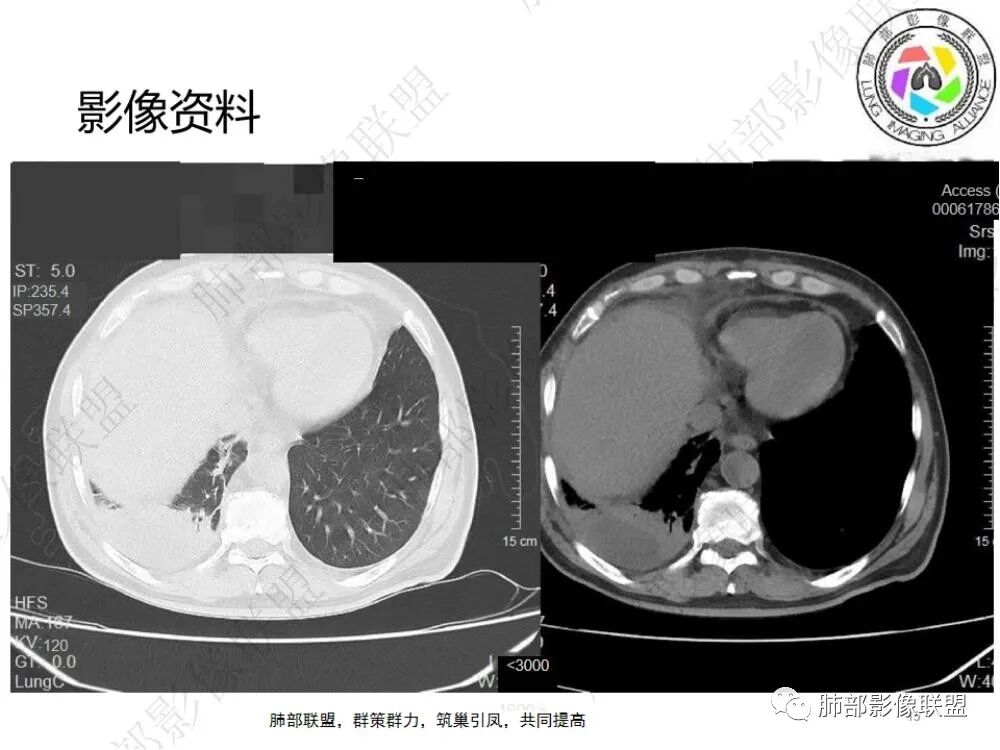

4.右侧胸腔积液,多包裹局限。

6.一周后复查变化较为明显。肺部实变影有所吸收,但胸腔积液增加明显,包裹于侧胸壁、纵隔旁及叶间裂。注意右肺下叶因积液推压明显(可惜未能提供薄层图片及矢状位图片)。

7.扫描范围内肝顶叶未见异常低密度区。